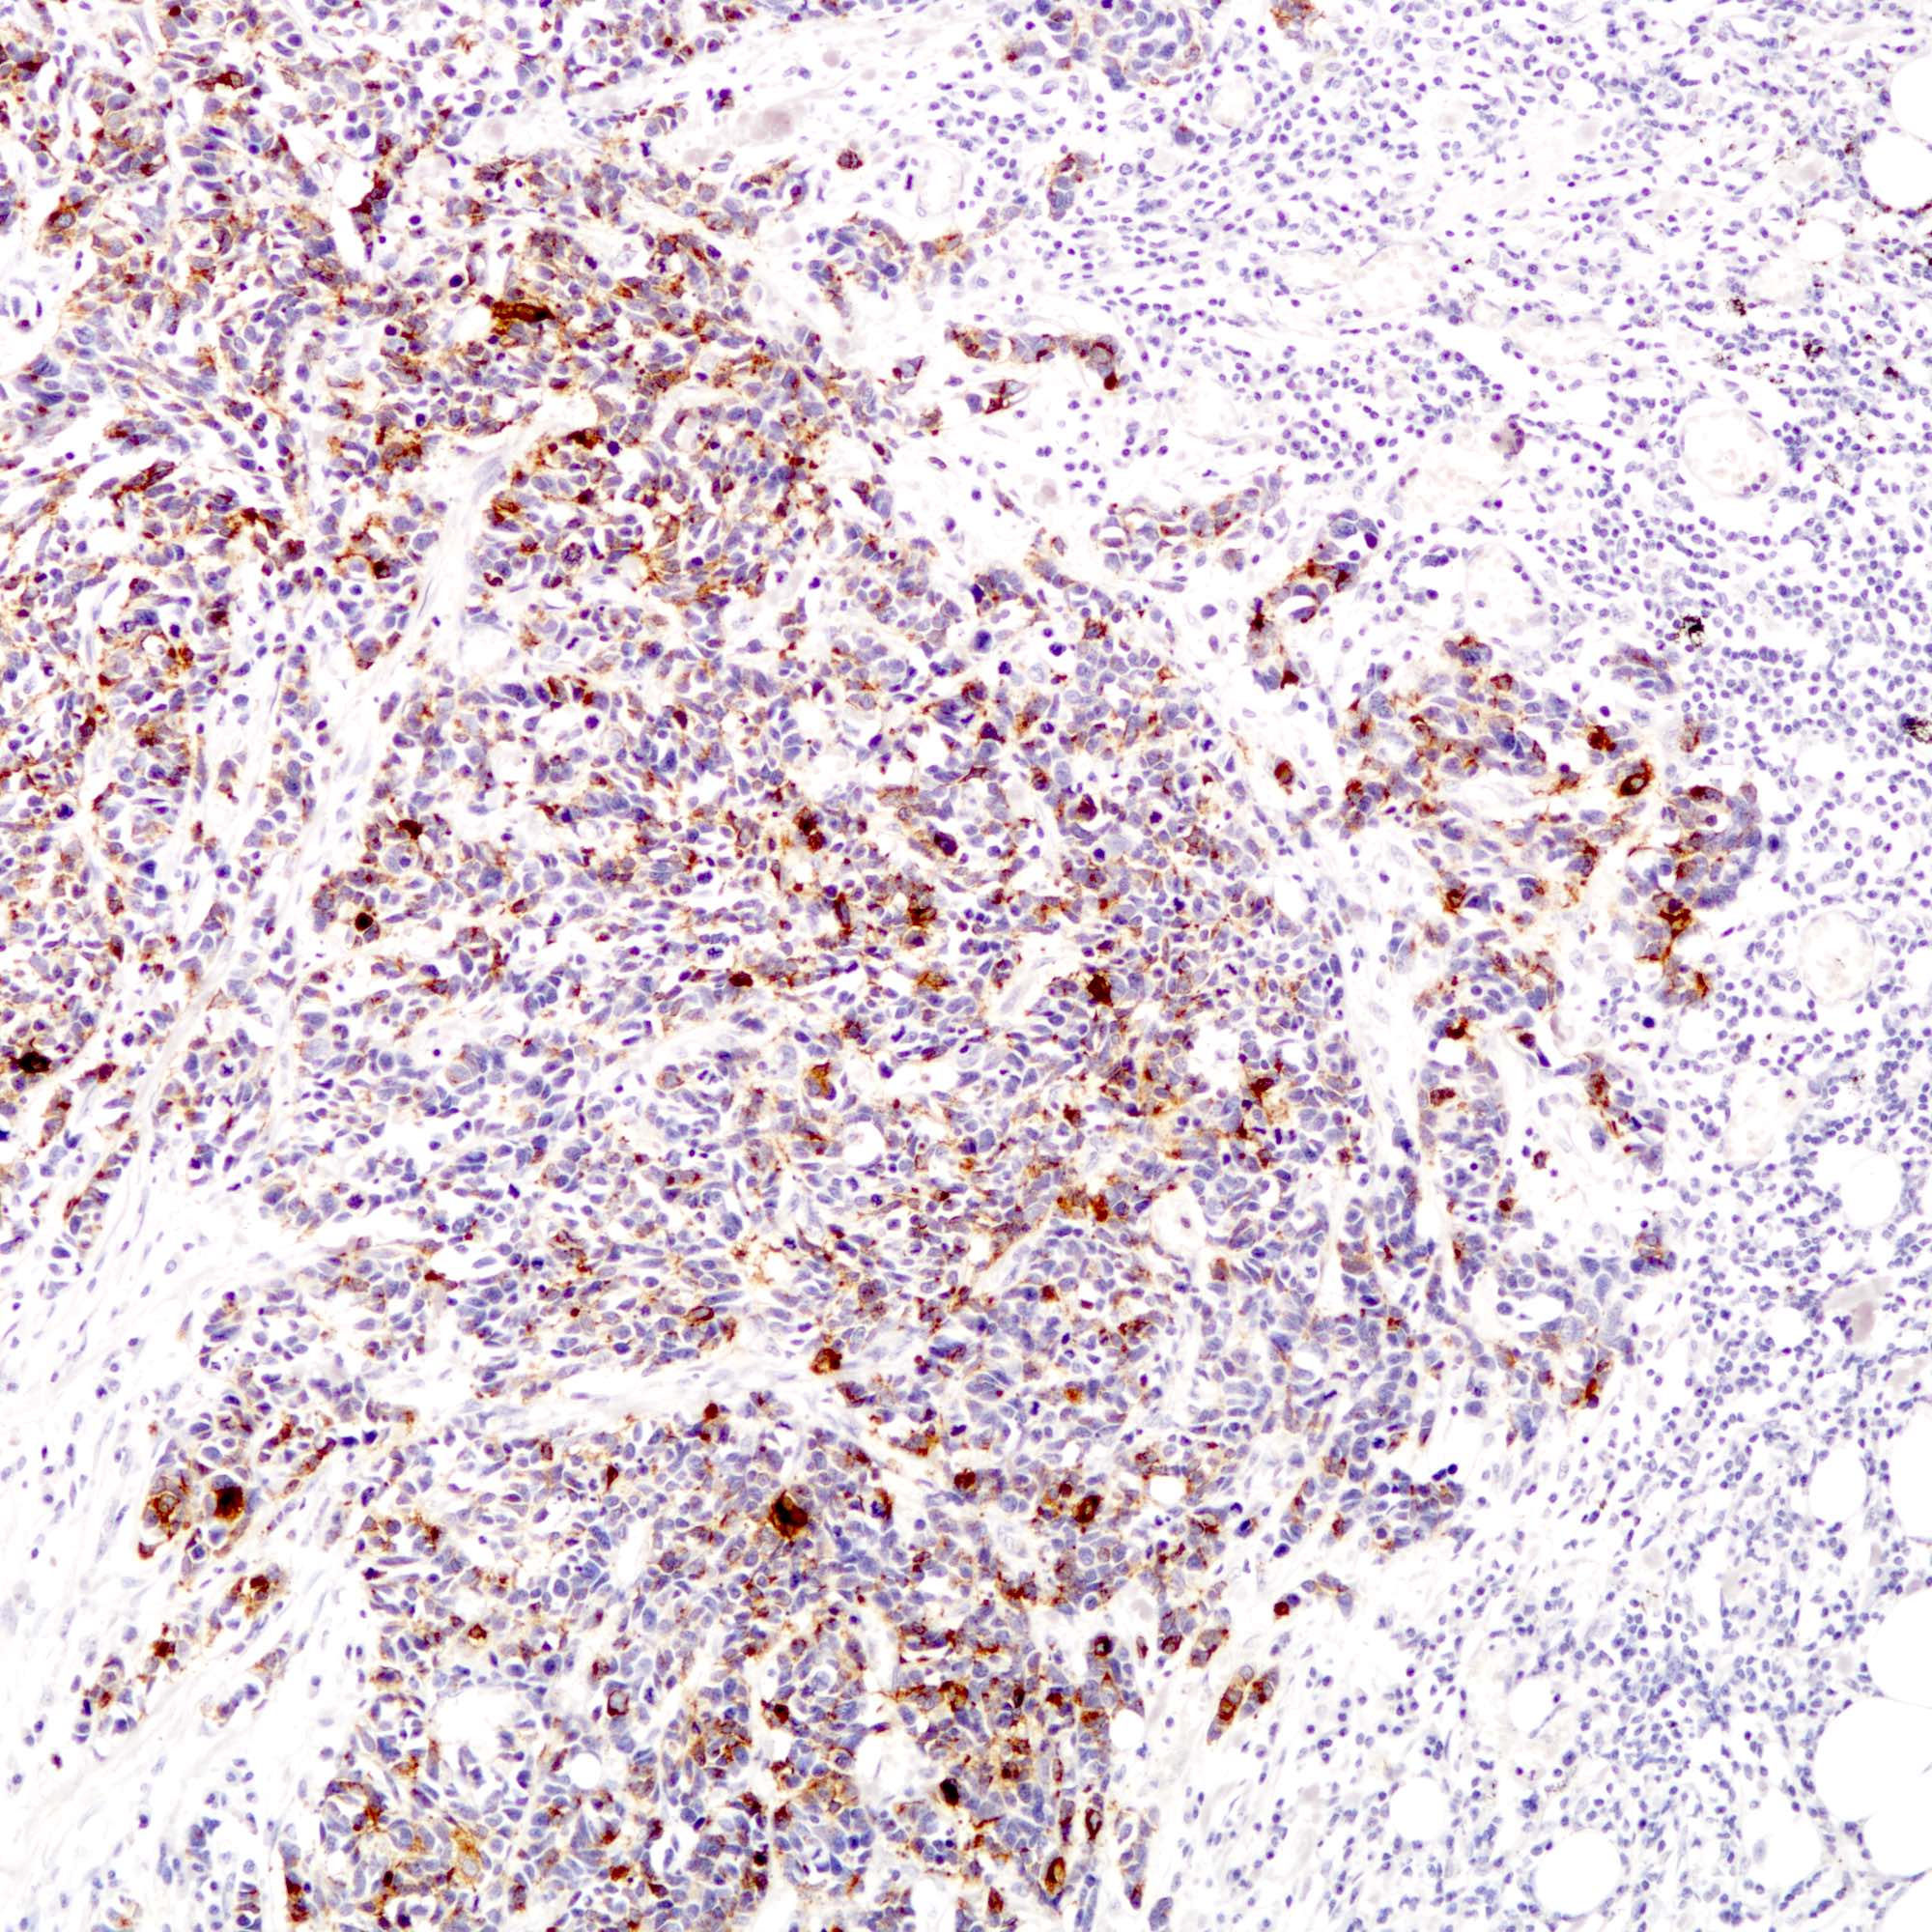

Contributed by Joshua J.X. Li, M.B.Ch.B., Gary M. Tse, M.B.B.S. and Kristen E. Muller D.O.

Small cell carcinoma

Large cell carcinoma

Positive stains

- Neuroendocrine markers:

- The tumor cells are diffusely positive for synaptophysin and focally positive for chromogranin.

- The tumor cells are diffusely positive for synaptophysin and focally positive for chromogranin.